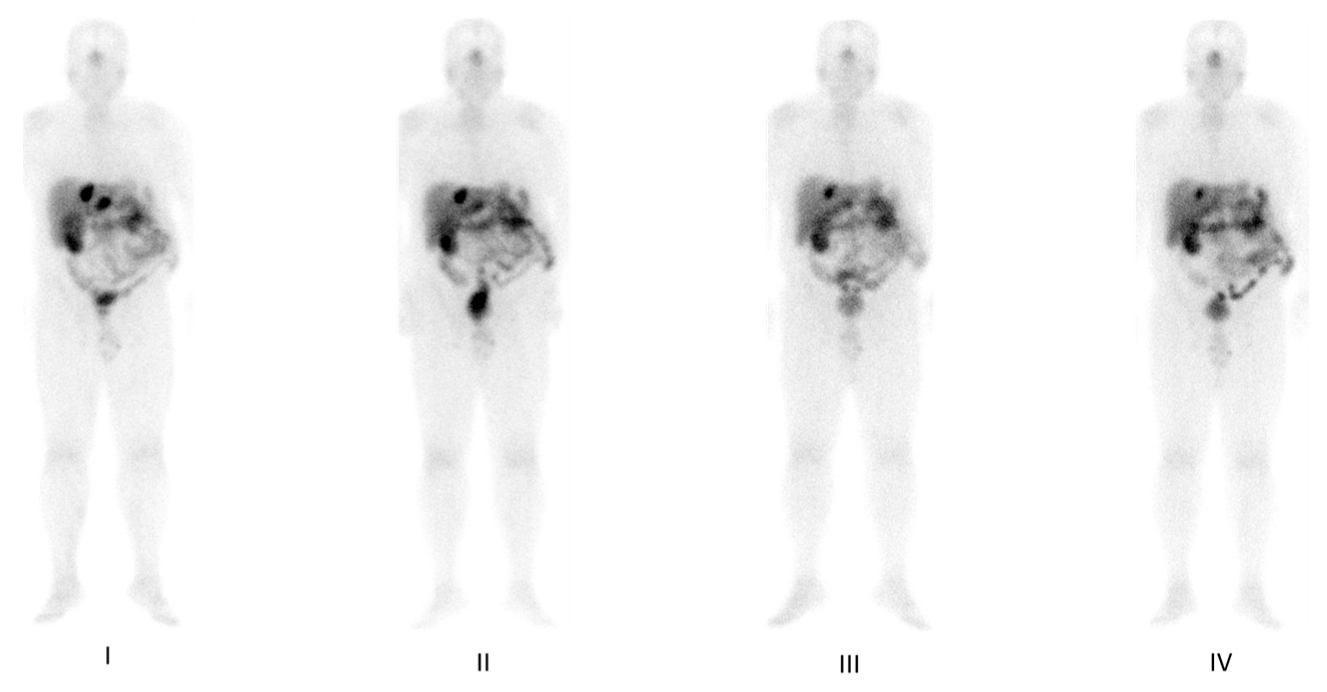

4. Functional Imaging by SST Analogs

5. Imaging Analysis

6. Functional Imaging by 18F-FDG PET/CT

7. PRRT by Radiolabeled Somatostatin Analogs